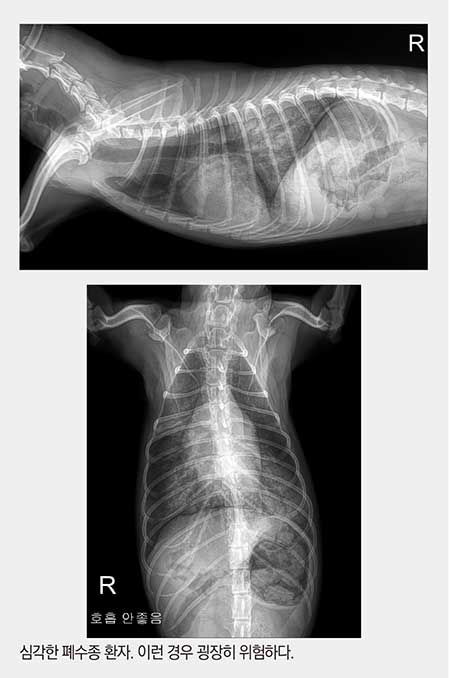

1. 폐수종

좌심실의 피가 좌심방으로 역류하고, 좌심방의 압력이 높아지면 폐울혈이 생기면서 폐에 물이 차게 된다. 물에 빠지는 것과 마찬가지 상태가 되어 호흡곤란으로 응급실에 내원한다. 운이 좋으면 약간의 폐수종 상태에서 “표정이 좀 이상해요, 간식을 안먹어요” 등의 증상을 호소하며 내원하지만, 어떤 아이들은 저산소증에 의해 곧 사망할 것 같은 상황으로 실려오기도 한다.

이런 경우 방사선 사진을 촬영하는 것조차도 위험해서 우선 iv 잡고 이뇨제 주면서 산소마스크를 쓰고, 호흡이 안정될 때까지(폐의 물이 좀 빠질 때까지) 기다린다. 병원까지 살아서 도착하는 것도 운이 좋은 경우에 속한다. 운명의 신이 병원에 오는 길에 아이를 데려가 버리기도 하니까.